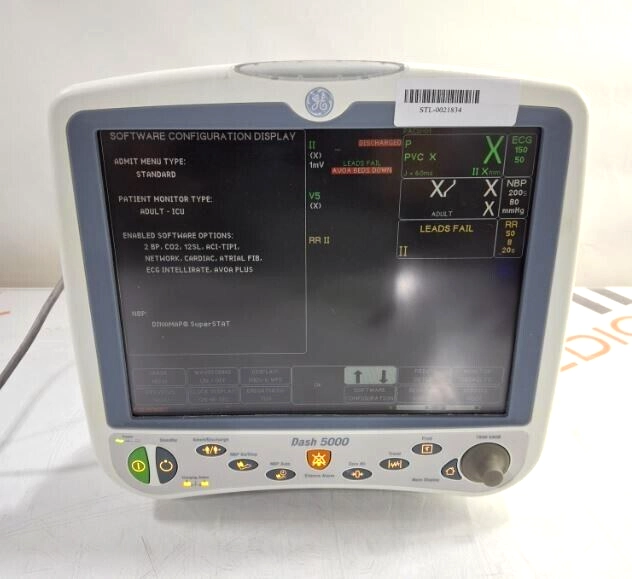

GE Healthcare Dash 5000 - Masimo SpO2 Patient Moni

$217.00

USD

GE Healthcare Dash 5000 - Masimo SpO2 Patient Moni

$217.00

USD

GE Healthcare Dash 5000 - GE/Nellcor SpO2 Patient

$217.00

USD

GE Healthcare Dash 5000 - GE/Nellcor SpO2 Patient

$217.00

USD